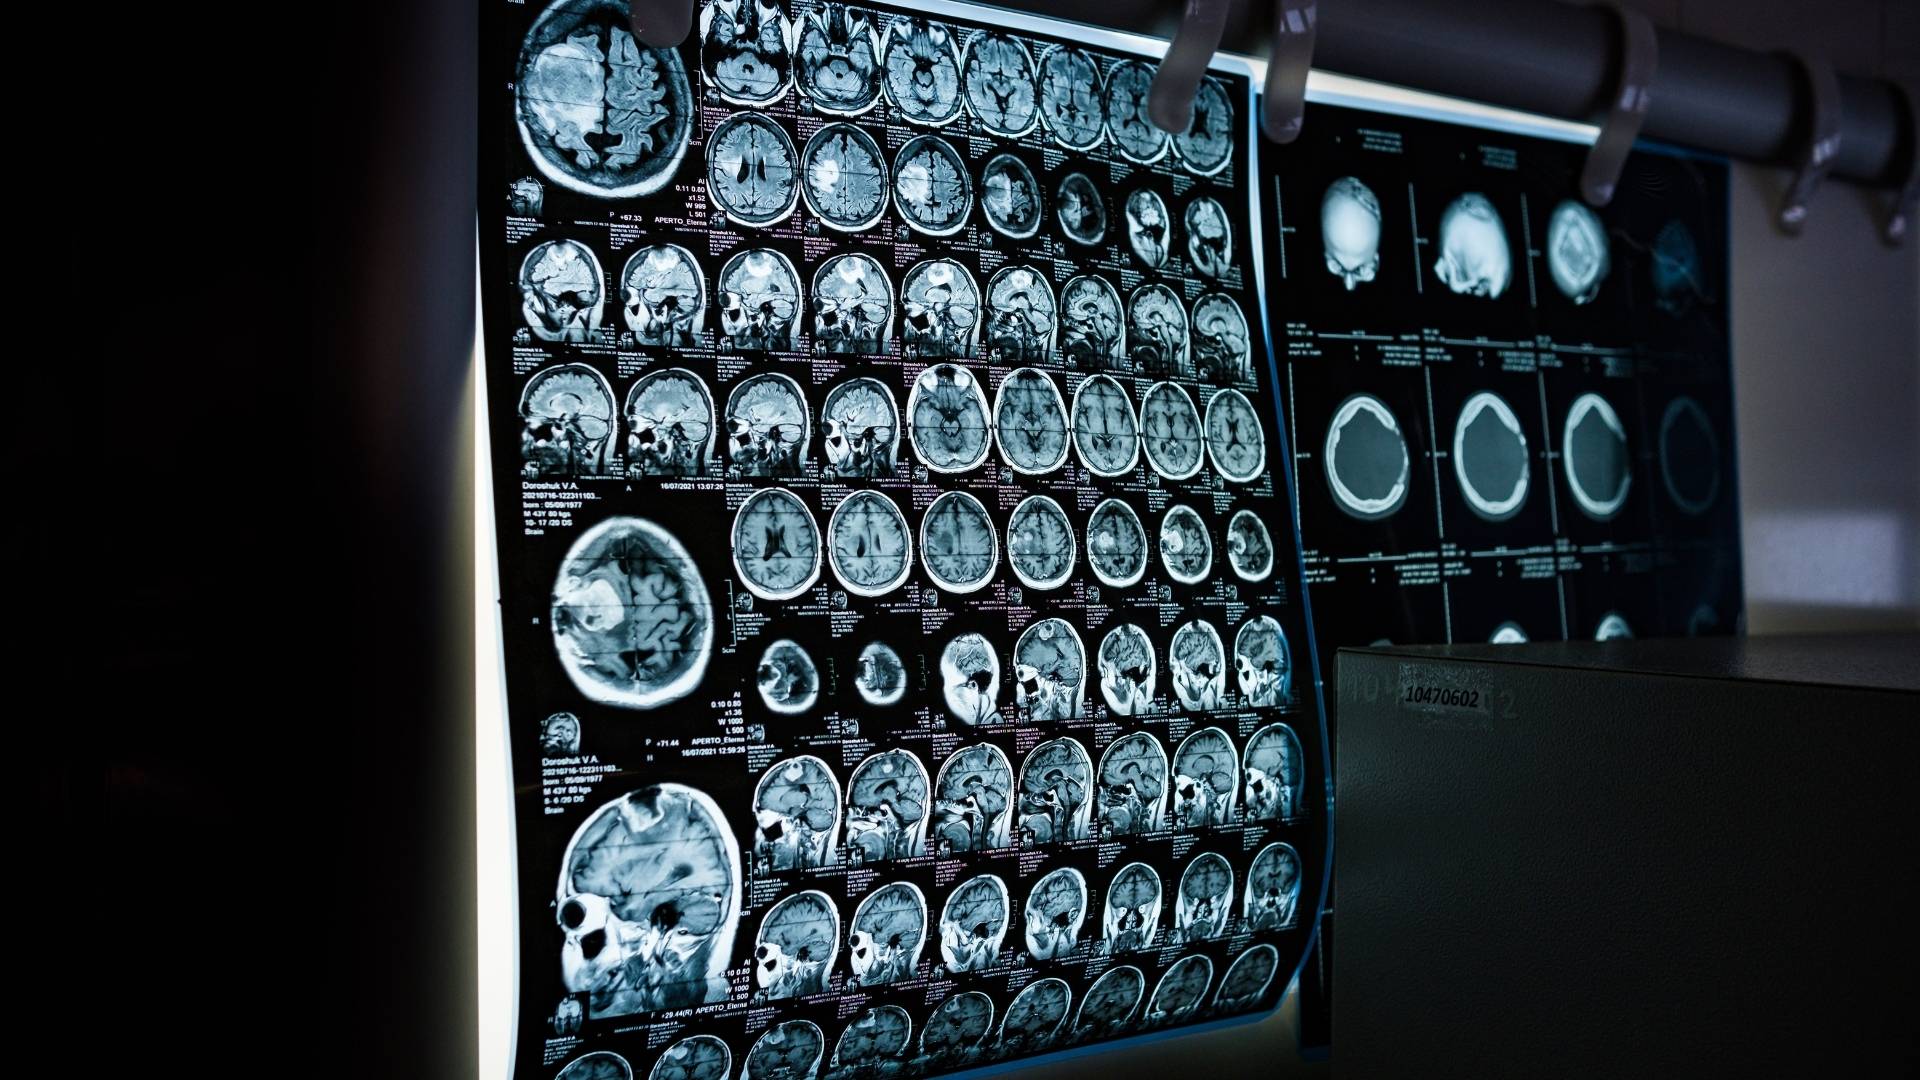

The Scan